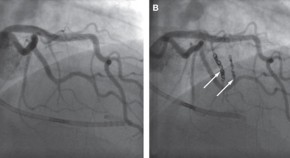

• Ramcharitar et al. describe the first case treated in the SECRITT I trial. The 63-year-old man presented with class II anginal symptoms and was diagnosed as having a culprit lesion in the left circumflex artery and a vulnerable plaque in the left anterior descending artery. The vulnerable plaque was treated with a self-expanding stent tailored to shield this type of plaque.